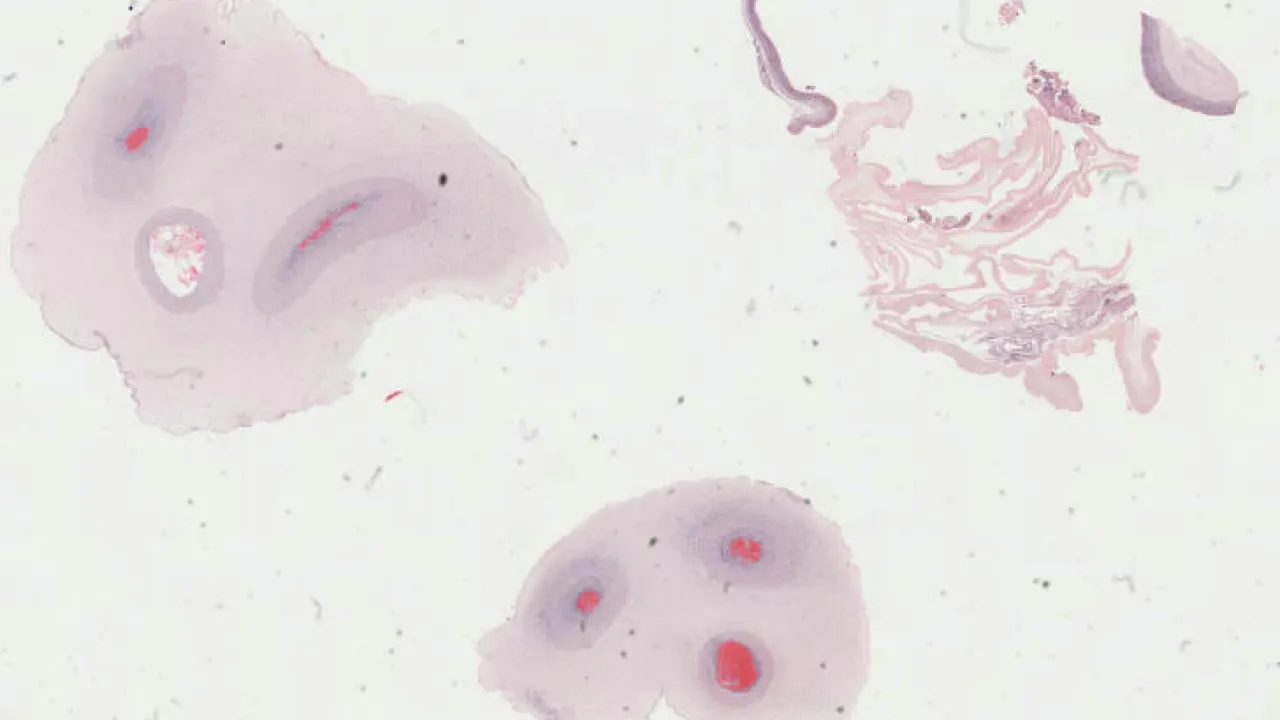

Liver, Hydatid disease, H&E stain

Liver, Hydatid disease, trichrome stain

Liver, Hydatid cyst